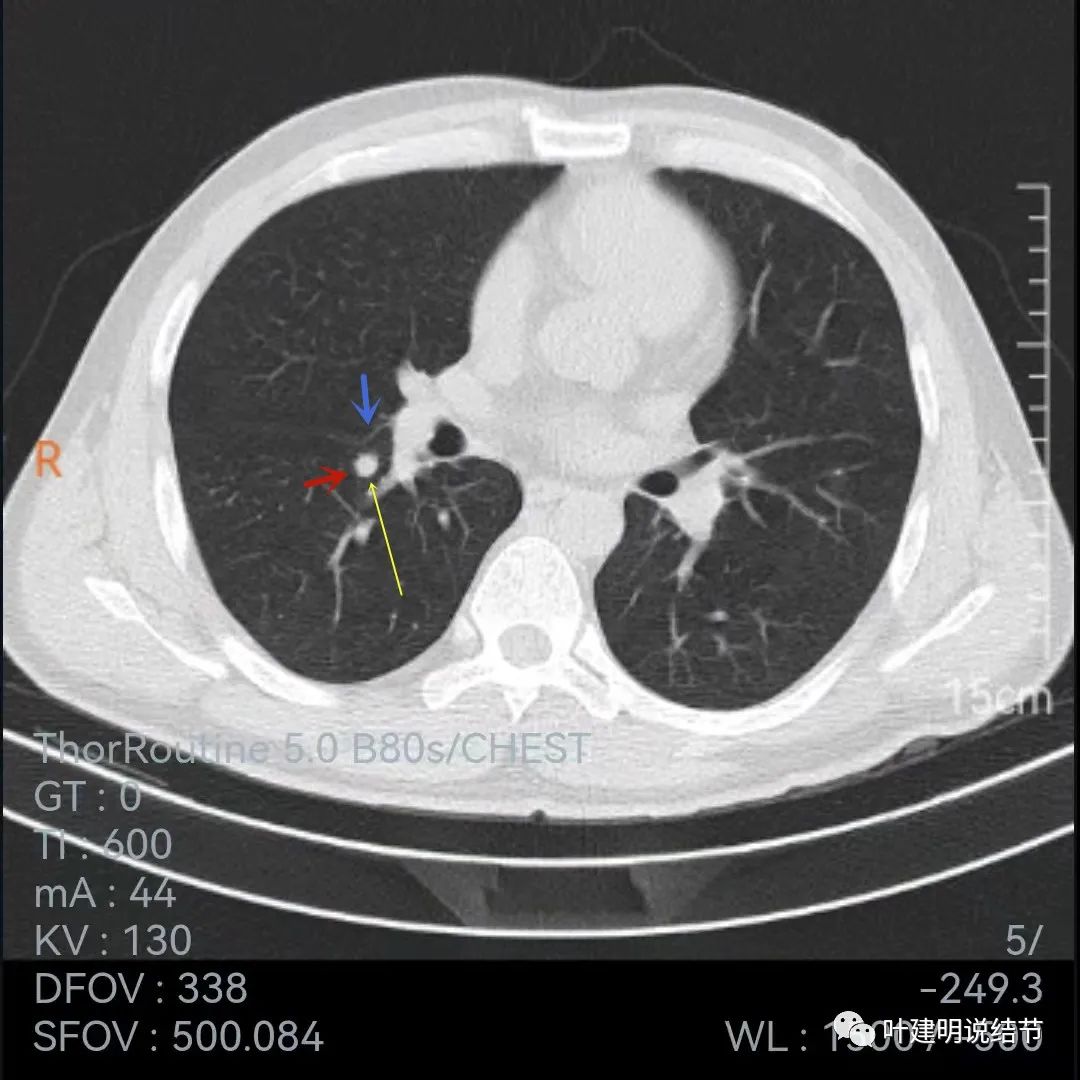

再看下面2020年7月的平扫片子:

非薄层的看,病灶还是小结节,实性,边缘似乎比前一年略有毛糙,胸膜轻微牵拉,黄色箭头所指似乎病灶中央的密度比周围部分略低,会不会是肉芽肿性炎伴有少许坏死?

再来看下面薄一点的,也是2020年7月的图像:

叶间胸膜牵拉

牵拉明显

中间密度略低(黄色箭头),前部边缘似有少许毛刺或毛糙的感觉(紫色箭头)

叶间胸膜牵拉凹陷

上图层面密度略不均

与前一年相比,病灶略有不同,感觉边缘粗糙起来,胸膜凹陷较前明显,但因为薄层与非薄层的区别,可比性略差。